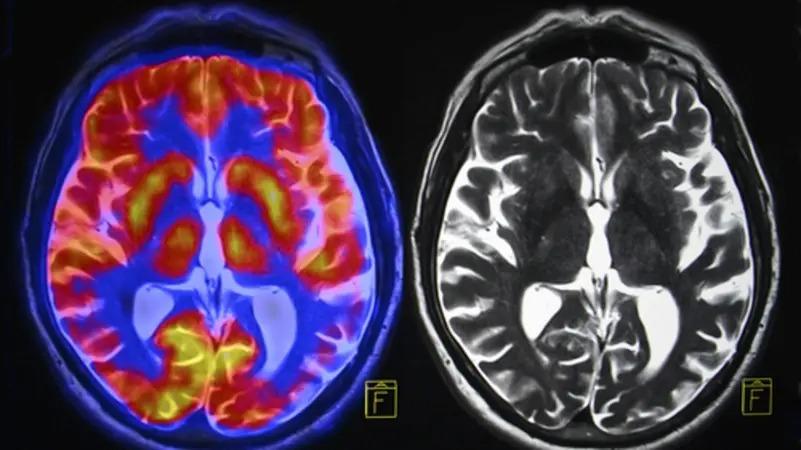

وقارن الباحثون فحوصات التصوير بالرنين المغناطيسي لـ 81 مراهقاً في الولايات المتحدة قبل الوباء، بين نوفمبر 2016 ونوفمبر 2019، مع 82 مراهقاً تم جمعهم بين أكتوبر 2020 ومارس 2022، أثناء الوباء ولكن بعد رفع الإغلاق، بحسب صحيفة “غارديان” البريطانية.

وبعد مطابقة 64 مشاركاً في كل مجموعة لعوامل تشمل العمر والجنس، وجد الفريق أن التغيرات الجسدية في الدماغ التي حدثت خلال فترة المراهقة، مثل ترقق القشرة ونمو الحُصين واللوزة، كانت أكبر في فترة ما بعد الإغلاق، مقارنة بمجموعة ما قبل الجائحة، مما يشير إلى تسريع مثل هذه العمليات. بعبارة أخرى، تقدمت أدمغتهم بشكل أسرع.